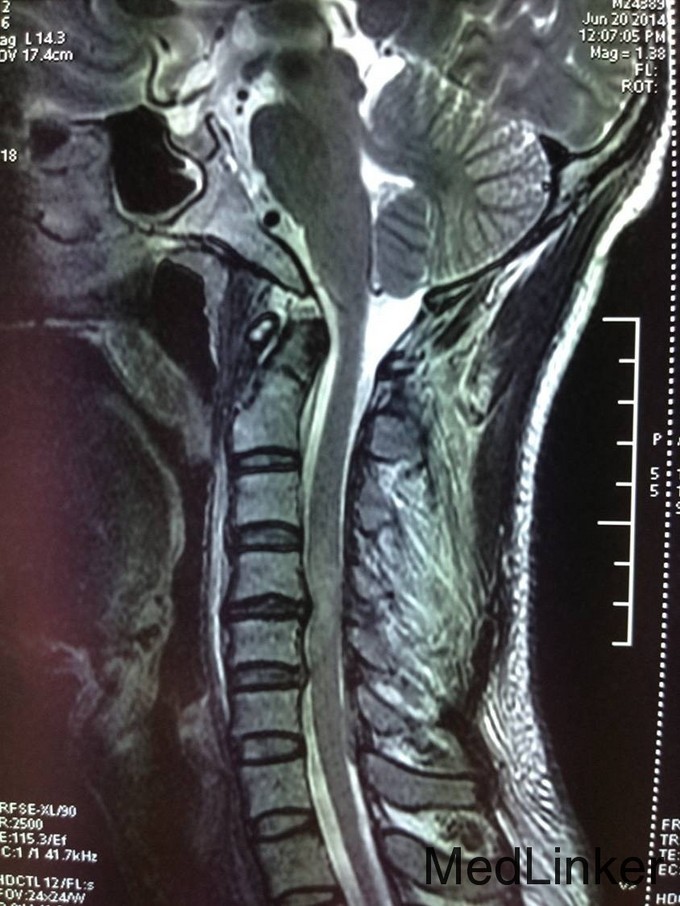

诊断:颈椎外伤(不全瘫);脊髓损伤 患者入院后完善相关检查,查无手术禁忌症后急诊行颈椎后路椎板减压椎管扩大单开门侧块螺钉内固定术,术后患者生命体征平稳,双上肢感觉疼痛,双下肢足趾肌力恢复到1级,术后3天后转入康复科继续康复治疗。

患者颈椎外伤不全瘫,应及早的行手术治疗,完善检查后可见MR的脊髓有高信号,应早期减除压迫,恢复神经功能。